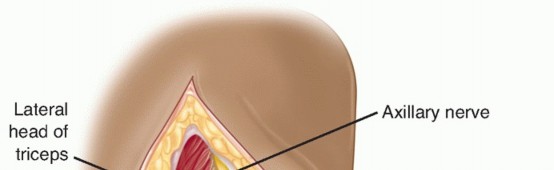

Stay sutures are inserted in the apex of the split to prevent the muscle from inadvertently splitting distally during retraction and damaging the axillary nerve.

The split edges of the deltoid muscle are retracted to reveal the underlying coracoacromial ligament. The coracoacromial ligament is detached from the acromion by sharp dissection.

The axillary nerve runs longitudinally in the quadrangular space beneath the teres minor.

The posterior circumflex humeral artery runs with the axillary nerve in the quadrangular space between the inferior border of the teres minor muscle and the superior boarder of the teres major muscle.